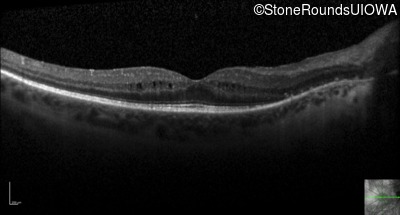

Optical Coherence Tomography - Right - 20/32

Exemplar / OCT Stack